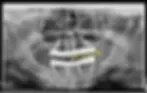

Post OP X-ray with Prosthesis: Panoramic X-ray showing All-on-4 implants supporting fixed full arch prosthetic teeth

Two implants were placed in a straight position in the anterior region, while the two posterior implants were tilted at approximately 45 degrees.

This angulation improves implant stability and allows better distribution of chewing forces.